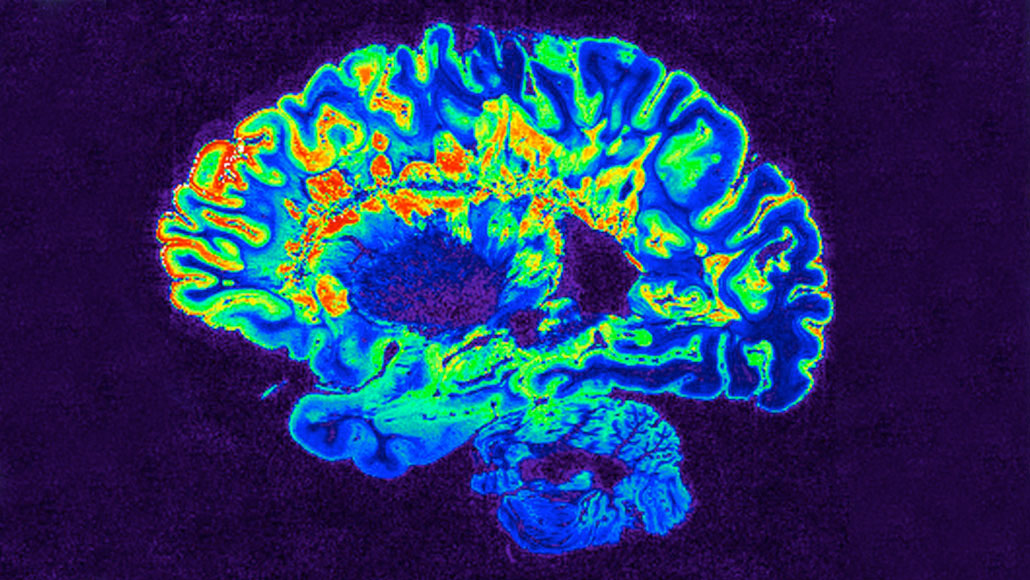

In multiple sclerosis, immune cells strip the brain’s nerve cells of their protective coating, forming lesions (shown in red in the center of this pseudocolored MRI brain scan).

Govind Bhagavatheeshwaran and Daniel Reich/NINDS/NIH